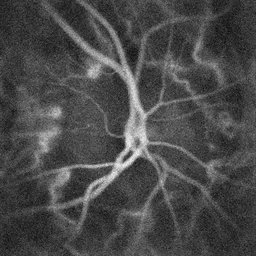

![]() Pulsatile blood flow in the central retinal artery revealed by laser Doppler holography | |

يوفر الشريان الشبكي المركزي الدم لجميع الألياف العصبية التي تشكل العصب البصري ، والذي يحمل المعلومات المرئية إلى النواة الركبية الوحشية للمهاد ، بما في ذلك تلك التي تصل فوق النقرة. يمكن الكشف عن تدفق الدم عن طريق تصوير الأوعية بالفلورسين أو تصوير دوبلر بالليزر [4].